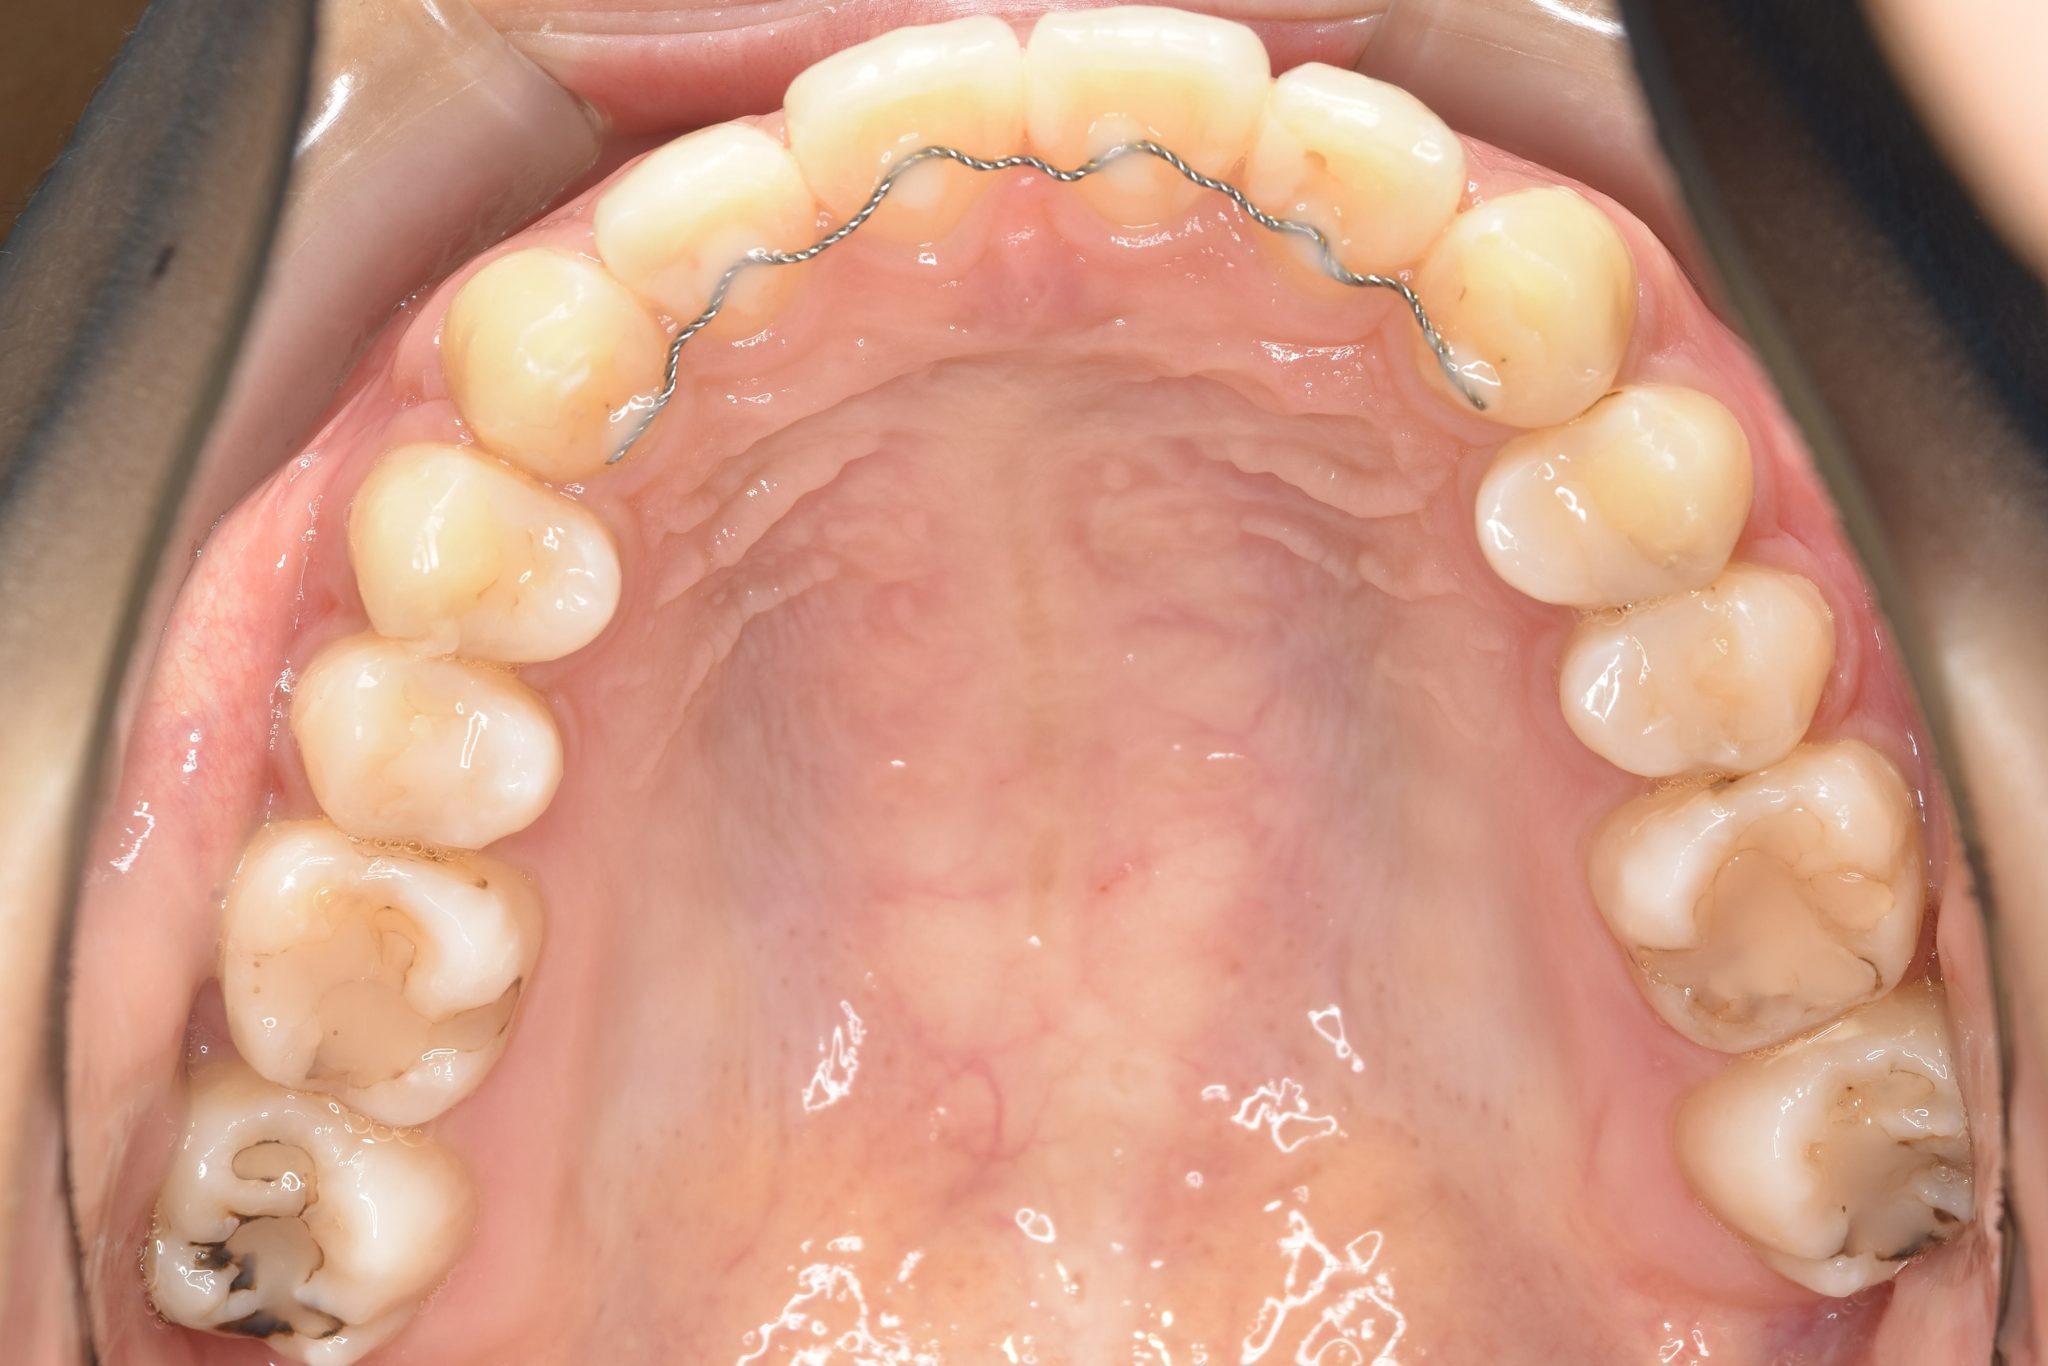

アフター

ワイヤー矯正治療|症例_009

施術内容 MSEと下顎リンガルアーチを用いて上下顎骨を拡大した。

その後マルチブラケット装置とミニインプラントを用いて非抜歯で歯牙を配列した。

下顎前歯が1本先天性欠損であったが、良好な咬合を獲得した。口元の突出感と鼻閉症状は改善された。